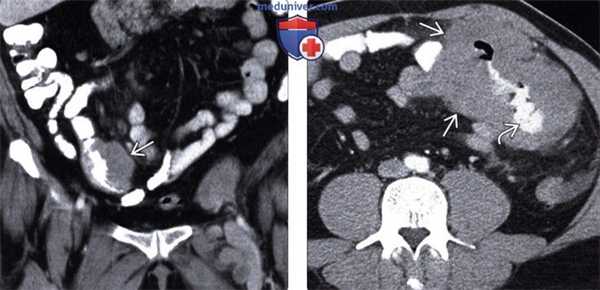

(Слева) При аксиальной КТ с контрастным усилением определяются гиподенсные мягкие ткани в виде «кожуры» вокруг обеих почек, классическое проявление периренальной лимфомы.

(Справа) При аксиальной КТ с контрастом определяется большое мягкотканное объемное образование вокруг правой почки, проявление периренальной НХЛ.

(Слева) При КТ с контрастным усилением в корональной плоскости визуализируется опухолевидное утолщение мягких тканей по краю подвздошной кишки. Обратите внимание на отсутствие обструкции кишки несмотря на значительное опухолевое поражение. Это характерное проявление лимфомы.

(Справа) На аксиальной КТ с контрастным усилением у ВИЧ-инфицированного пациента выявлено большое изъязвленное образование с наличием контраста в просвете тонкой кишки. Обратите внимание на типичное аневризматическое расширение просвета пораженной кишки вследствие опухолевой инфильтрации. Это часто встречающееся проявление лимфомы кишечника.